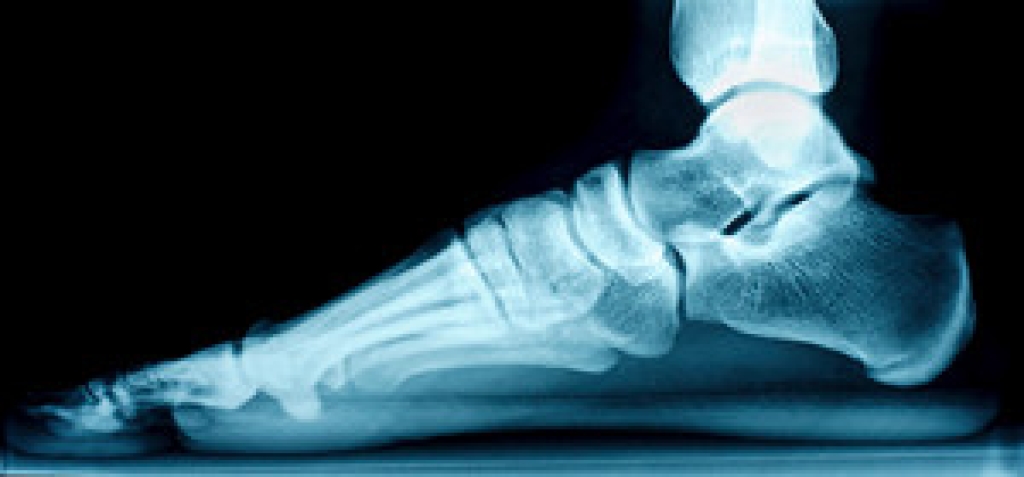

Hammertoe is a foot deformity that occurs due to an imbalance in the muscles, tendons, or ligaments that normally hold the toe straight. It can be caused by the type of shoes you wear, your foot structure, trauma, and certain disease processes.

Risk Factors

- Age – The risk of hammertoe increases with age

- Sex – Women are more likely to have hammertoe compared to men

- Toe Length – You are more likely to develop hammertoe if your second toe is longer than your big toe

- Certain Diseases – Arthritis and diabetes may make you more likely to develop hammertoe

Treatment

If you have hammertoe, you should change into a more comfortable shoe that provides enough room for your toes. Exercises such as picking up marbles may strengthen and stretch your toe muscles. Nevertheless, it is important to seek assistance from a podiatrist in order to determine the severity of your hammertoe and see which treatment option will work best for you.